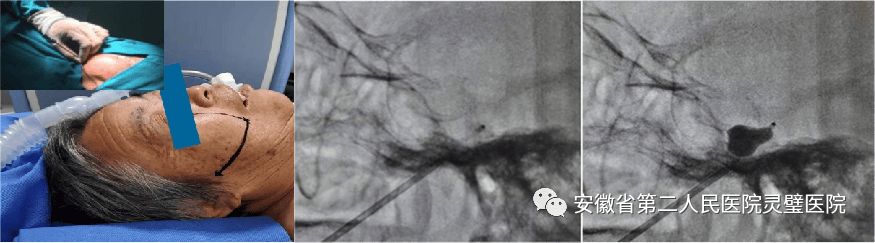

颈内动脉内膜剥脱术

脑血管病亚专业组紧跟国际前沿,目前全面开展颅内动脉瘤、脑动静脉畸形、硬脑膜动静脉瘘等脑血管病的外科及血管内治疗,尤其对复杂颅内动脉瘤,灵活运用支架及球囊辅助、双微导管、液态栓塞剂栓塞、覆膜支架等技术,取得良好效果。开展烟雾病血管搭桥、颈内内膜剥脱术等脑血管外科手术。